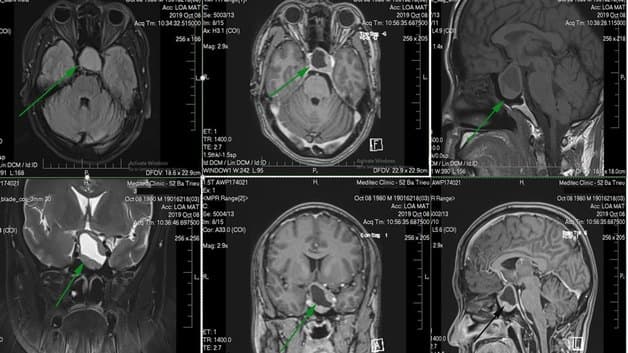

Chụp cộng hưởng từ (MRI) là kỹ thuật chẩn đoán y khoa sử dụng từ trường và sóng radio tạo thành hình ảnh giải phẫu cơ thể. Khác với chụp X-quang hay chụp cắt lớp vi tính (CT), phương pháp này không sử dụng tia X nhưng vẫn có thể cho phép phát hiện các vấn đề bất thường bên trong cơ thể, kể cả những bất thường ẩn sau lớp xương.

Điểm đặc biệt đó chính là hình ảnh thu được từ chụp cộng hưởng từ có độ phân giải cao và chi tiết về những hiện trạng của các bộ phận trên cơ thể. Chính vì thế, có thể áp dụng chẩn đoán với hầu hết các bệnh lý, đặc biệt là những bệnh lý như:

– Hình ảnh có độ sắc nét cao, có khả năng tái tạo 3D chi tiết

– Đánh giá tốt các tổn thương và hệ thống thần kinh

– Đánh giá tốt các cơ quan rất nhỏ bên trong hệ thần kinh hay mạch máu.